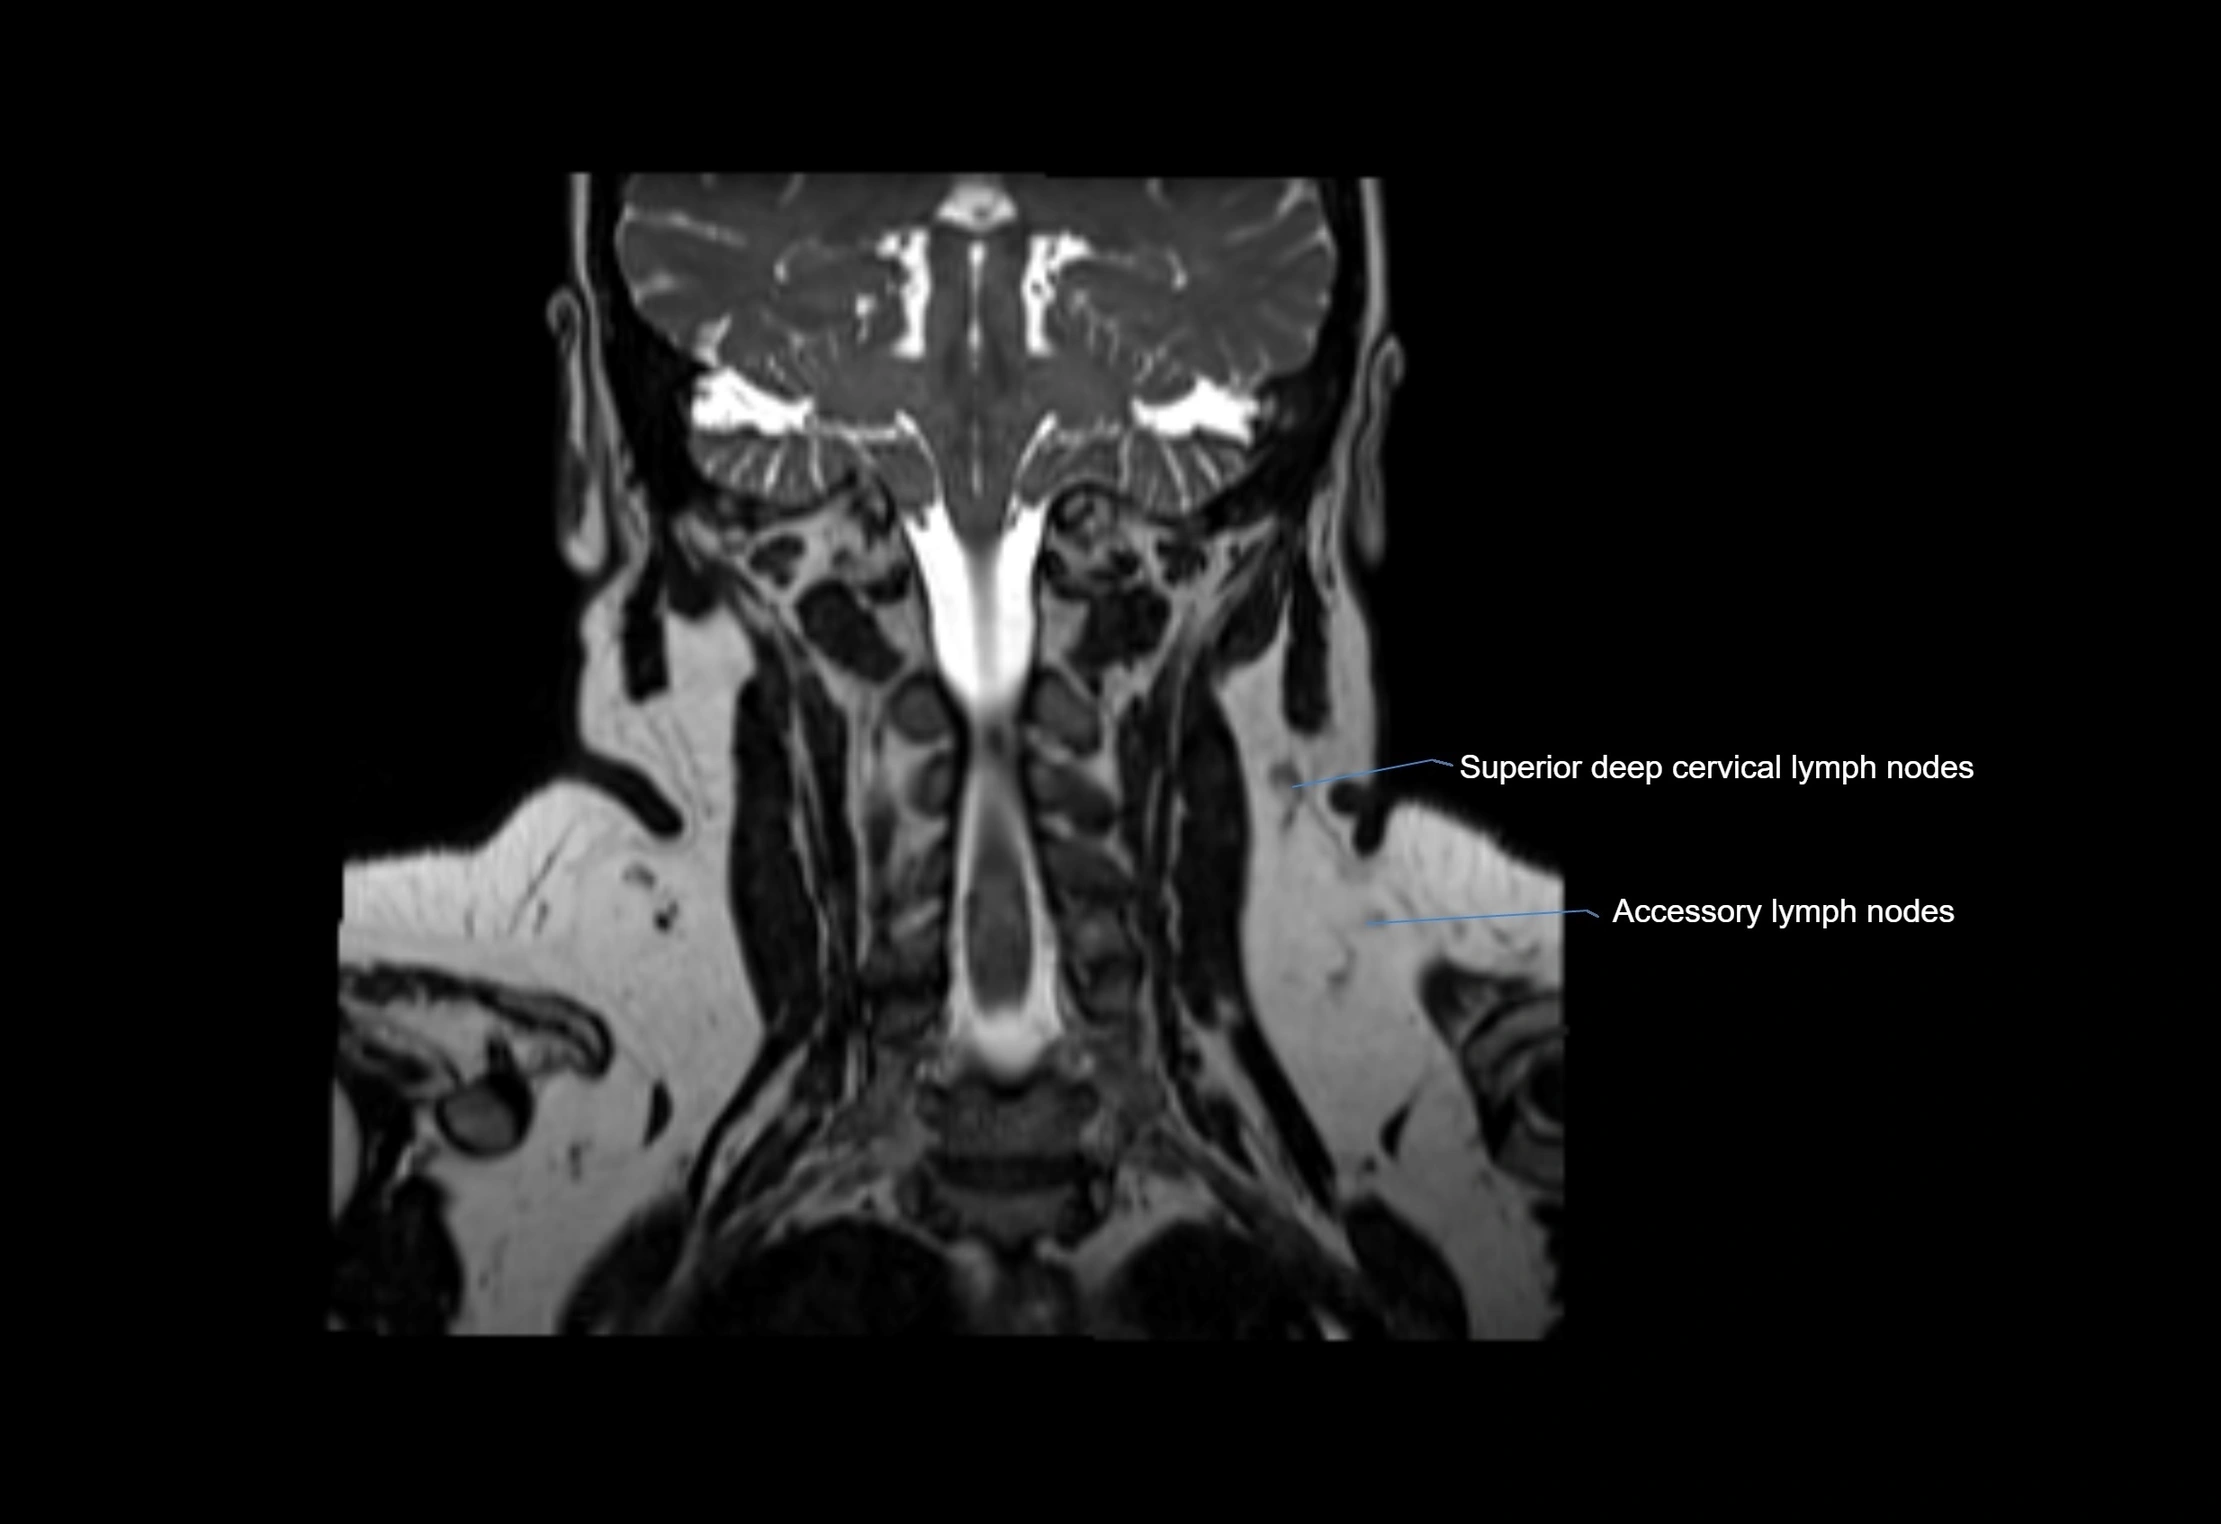

MRI images

image